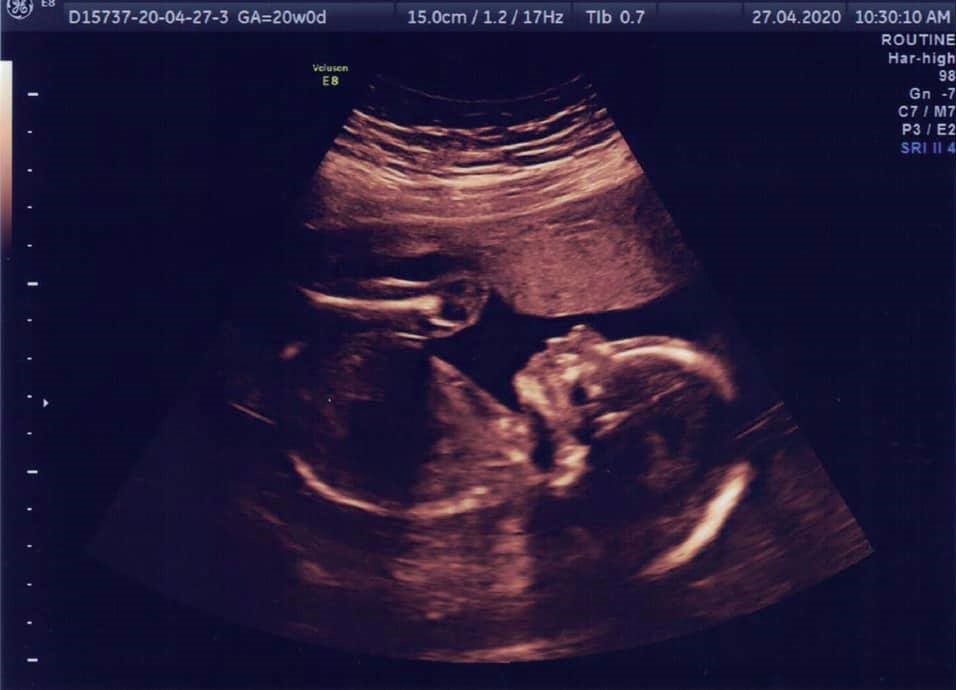

My heart jumped and my head sighed. I frantically rung my husband to give the good news as he was working away that day. Our little rainbow girl. The first for our family as my brother has 3 boys and my husbands brother has 2 boys! What a special little one she is.

I am 22 weeks as I write this today.

It has to be said that there are always doubts, fears, anxieties, uncertainties and the worry of something coming along at any moment to throw us into chaos. After all, previous experience has paved the way for this pregnancy to be fraught with emotional hurdles and fears. But we are quietly confident with each week that passes and our little girl fighting… kicking…. moving her way towards the day when we finally get to meet her and hold her in our arms.

For now, I will sign off with this little picture to remind us all that “there is some good in this world…and it’s worth fighting for”